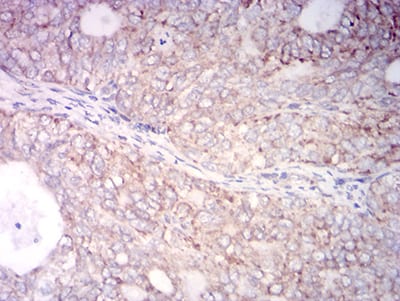

分类: 科研抗体货号: 31757别名: K18; CK-18; CYK18应用: WB,IHC,IF,FCM反应种属: Human

分类: 科研抗体货号: 31772别名: K18; CK-18; CYK18应用: WB,IHC,IF,FCM反应种属: Human